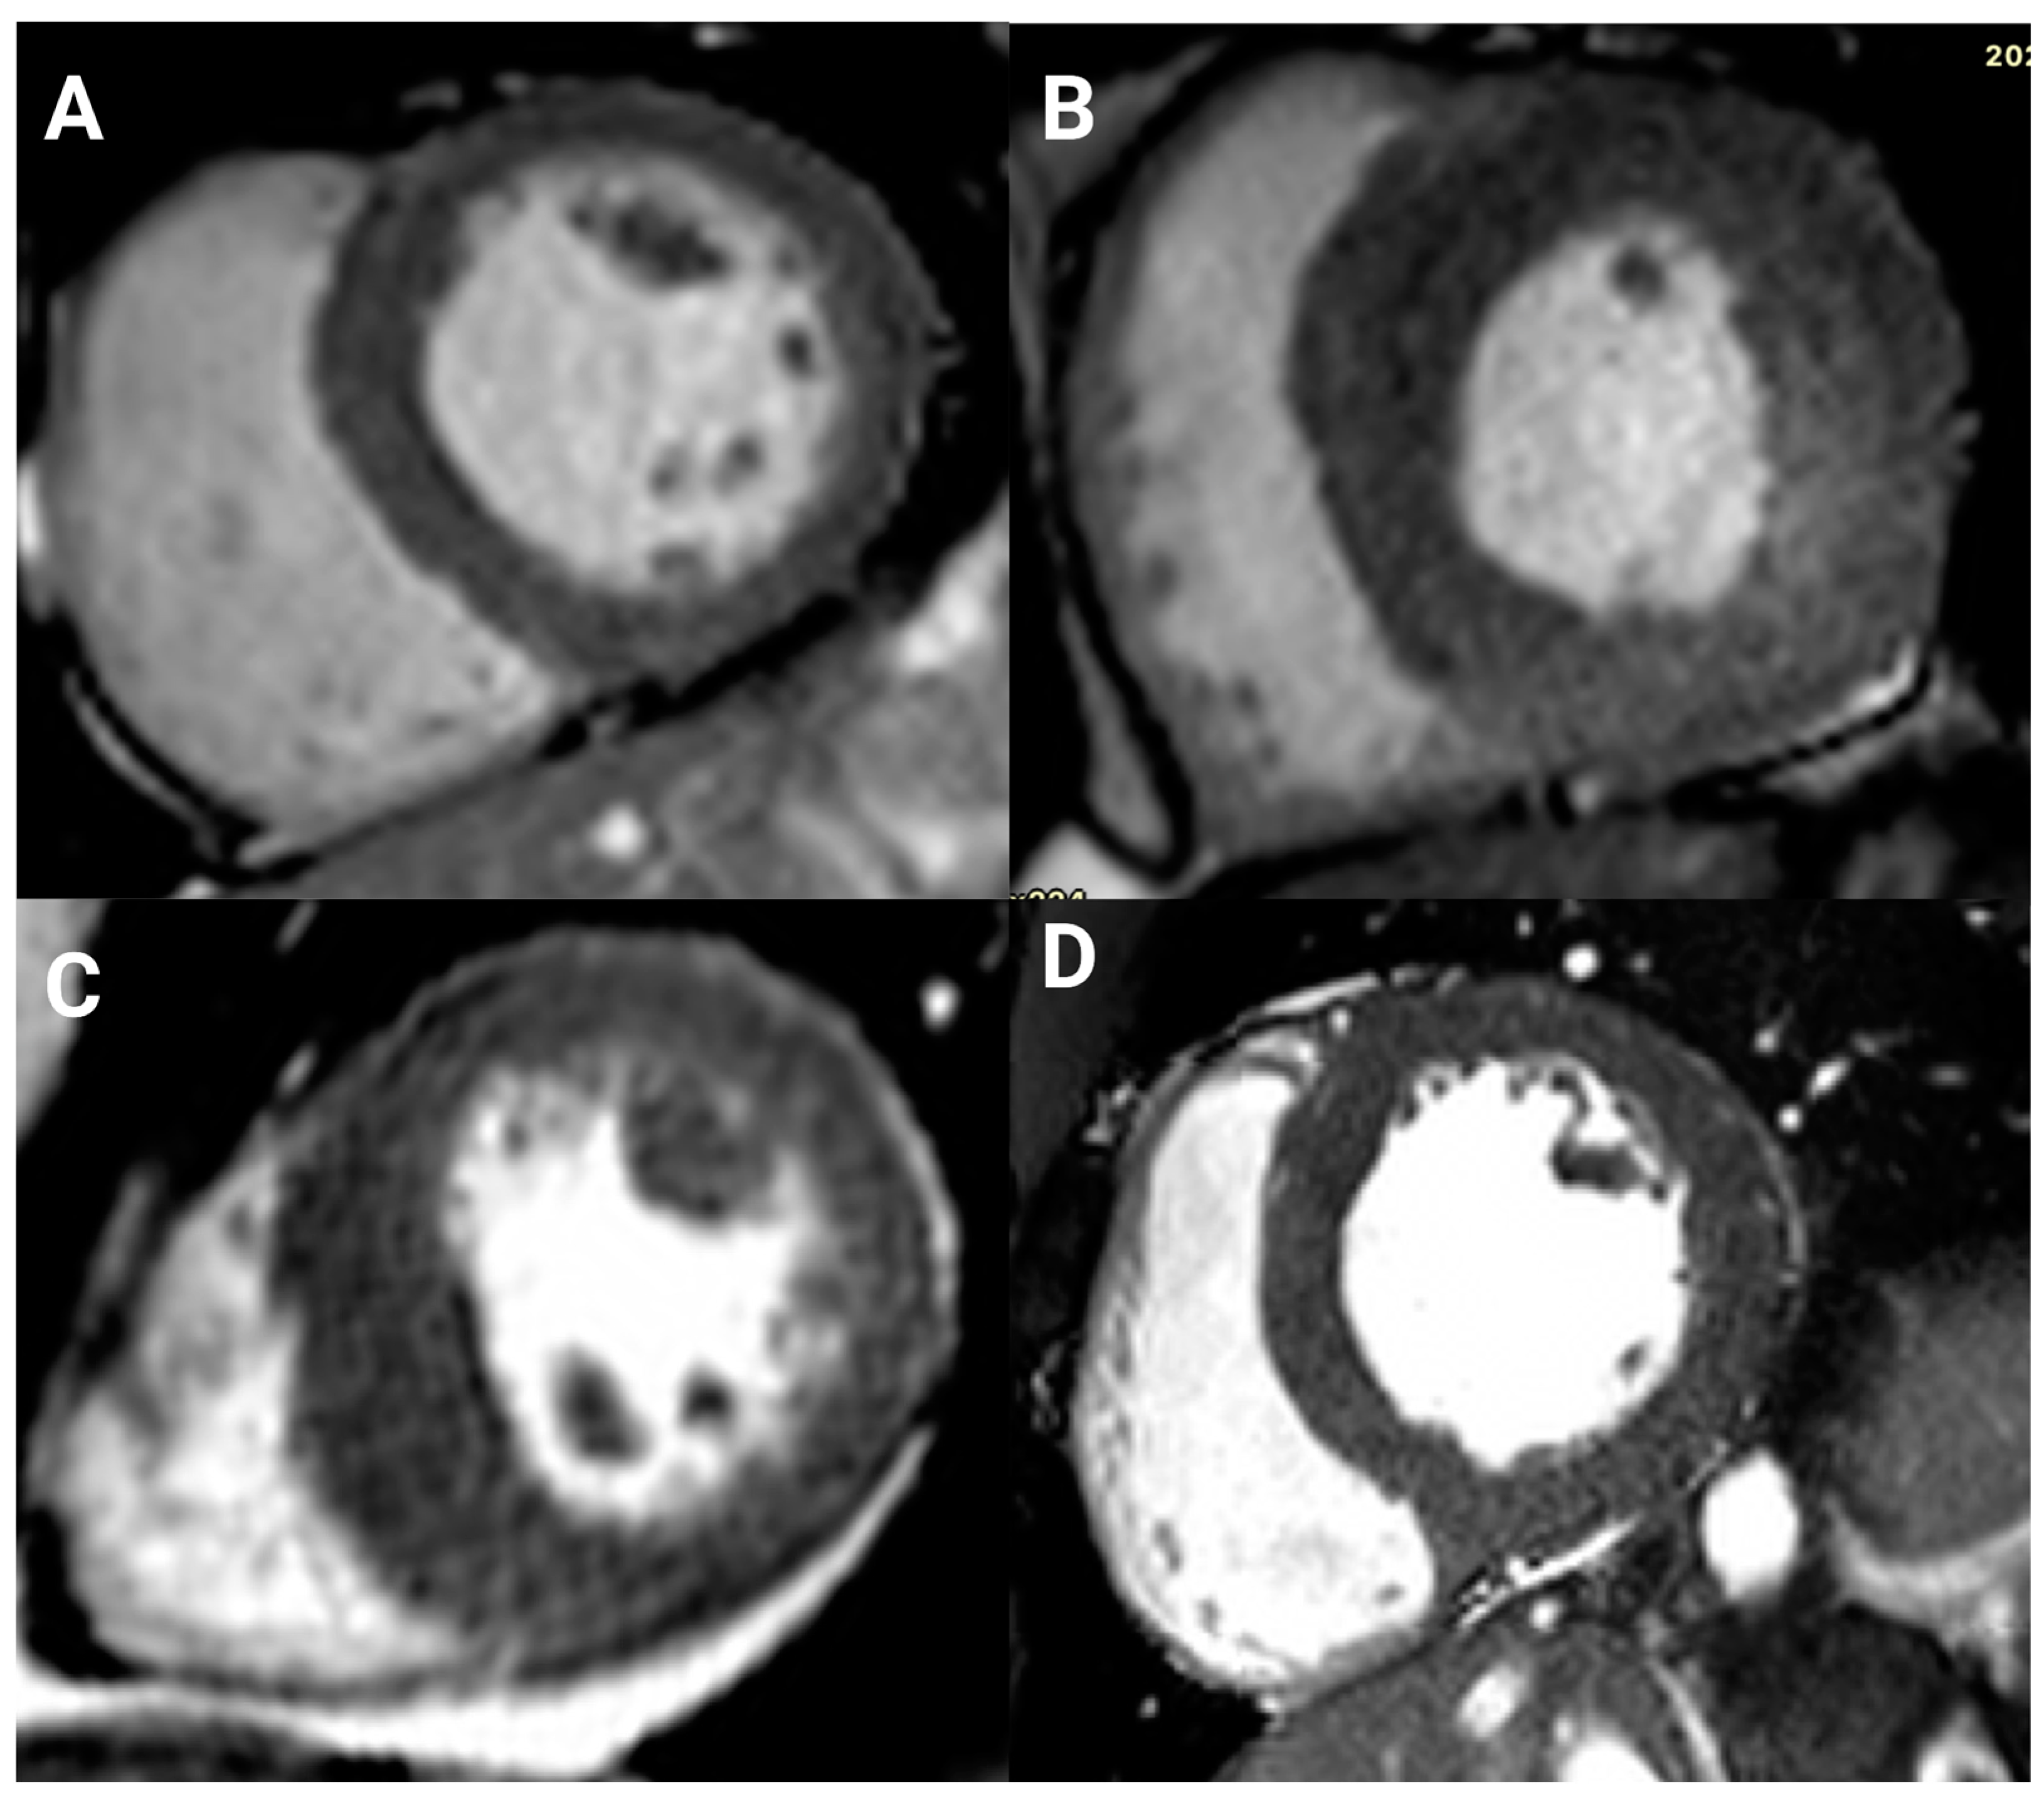

3.3. Late Gadolinium Enhancement

| LGE, n/contrast study, n (%) | 52/69 (75) | 8/18 (44) | 44/51 (86) | <0.001 |

| Ischemic pattern | 11/69 (16) | 0 (0) | 11/51 (22) | |

| Nonischemic pattern | 41/69 (59) | 8/18 (44) | 33/51 (65) |

| n = 52 (%) | |

|---|---|

| 11 (21.2) |

| Subendocardial with microvascular obstruction | 1 (1.9) |

| Transmural | 1 (1.9) |

| Transmural, mid wall, and right ventricular insertion point | 1 (1.9) |

| Transmural and right ventricular insertion point | 1 (1.9) |

| Transmural with microvascular obstruction | 5 (9.6) |

| Transmural and subendocardial | 1 (1.9) |

| Focal transmural and right ventricular insertion point | 1 (1.9) |

| 41 (78.8) |

| Right ventricular insertion point | 13 (25) |

| Focal and right ventricular insertion point | 1 (1.9) |

| Mid wall and right ventricular insertion point | 17 (32.7) |

| Patchy mid wall | 7 (13.5) |

| Focal, mid wall, and right ventricular insertion point | 1 (1.9) |

| Subepicardial, mid wall, and right ventricular insertion point | 1 (1.9) |

| Subepicardial | 1 (1.9) |